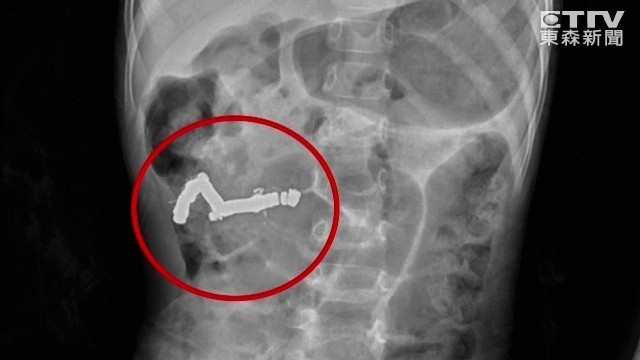

王小弟8月間感冒,父親到藥局買磁力貼布想幫他緩解症狀,未料他扯掉磁石吞下肚;從X光片左下角處很明顯看出長長一條異物,頭端成彎曲形狀,王小弟因此被折騰得哇哇大哭。

這一串一顆顆如鈕扣般的磁石,被男童當成巧克力糖吞下肚,因為吸力讓腸道打結、糾成一團,經手術取出後,近20顆黏在一起的磁石長約5.7公分(2英寸)。